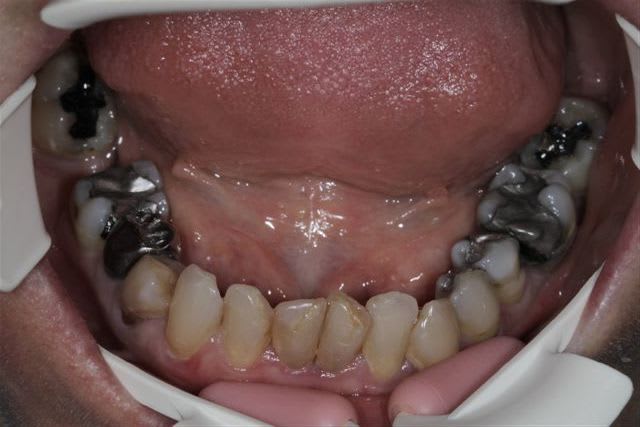

N'hésitiez pas çà me donner votre avis, patiente 47 ans ne supporte plus ses antérieurs, maquillées à la résine il y a quelques années.

Pas de demande concernant l'occlusion, ni les postérieurs, à fait des économies et veux s'offrir "un sourire", sur fond propre budget envisageable au départ 4000€

Vu les axes actuels des antérieures, soit tu gardes la même forme et les mêmes axes et tu auras de dents assorties mais pas vriament plus esthétiques. Sinon c'est ortho et la totale. Si tu changes la forme sans amélioration de l'esthétique ce sera l'echec mécanique assuré.

Je ne saurais pas quoi proposer à cette patiente si elle arrivait sur mon fauteuil.

Je suis assez d'accord avec Ceramik, ce qui me saute aux yeux,outre l'esthétique bien sur, ce sont les courbes occlusales de la patiente, notamment secteur 2 et 3 en postérieurs(26 ne semble pas en occlusion, et 27 sur une pointe).

Le secteur antérieur doit donc supporter pas mal de contraintes... d'autant plus que le guide incisif semble assez fermé.

Perso, je ne toucherai à rien en antérieur,( d'autant plus avec du tout céram) tant que les courbes postérieures ne sont pas rétablies.

pour moi, réhabilitation globale.

Paro ++

refaire les courbes occlusales

en antérieur, faire un compromis pour légèrement corriger la classe 2.

à mon avis, plus de 4000 euros.